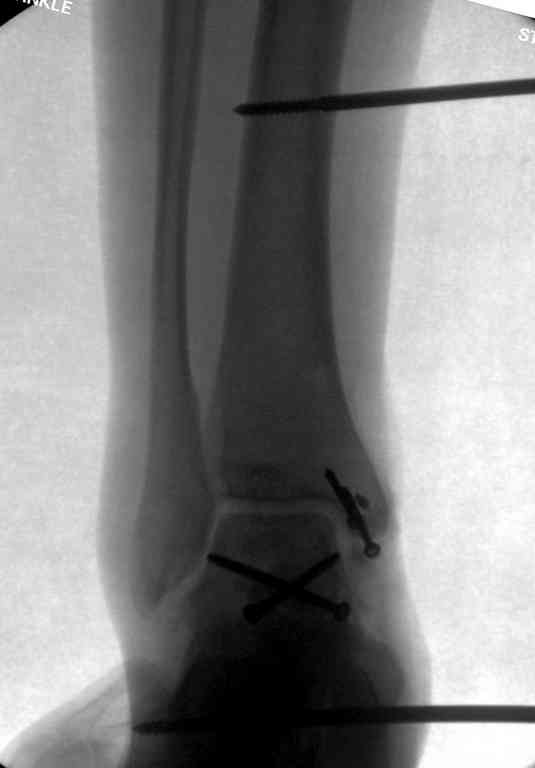

Вчера провели фиксацию.

Из-за многооскольчатости дистальной части малоберцовой, где невозможно было провести фиксацию шурупами, перелом зафиксирован подпирающей пластиной, которая должна служить дополнением отсутствующей дистальной части малоберцовой (lateral cortex substitute).

Для стабильности два шурупа на синдесмоз.

Медиальную рану с приближенными краями продолжаем вакуумировать (KCI). Наружный фиксатор оставлен на пару недель, надеюсь, небольшая рана будет гранулировать и закроется без кожной пластики. Фиксация медиальной ложыжки не планируется.

Прооперировали таранную кость, доступ внутренний без пересечения внутренней лодыжки. Хотя покаялись, что не пошли на остеотомию лодыжки внутренней. Винт

провели через небольшой передний доступ.

Джолдас, какими доступами вы пользовались? Какой срок иммобилизации по вашему мнению необходим в моем представленном случае?